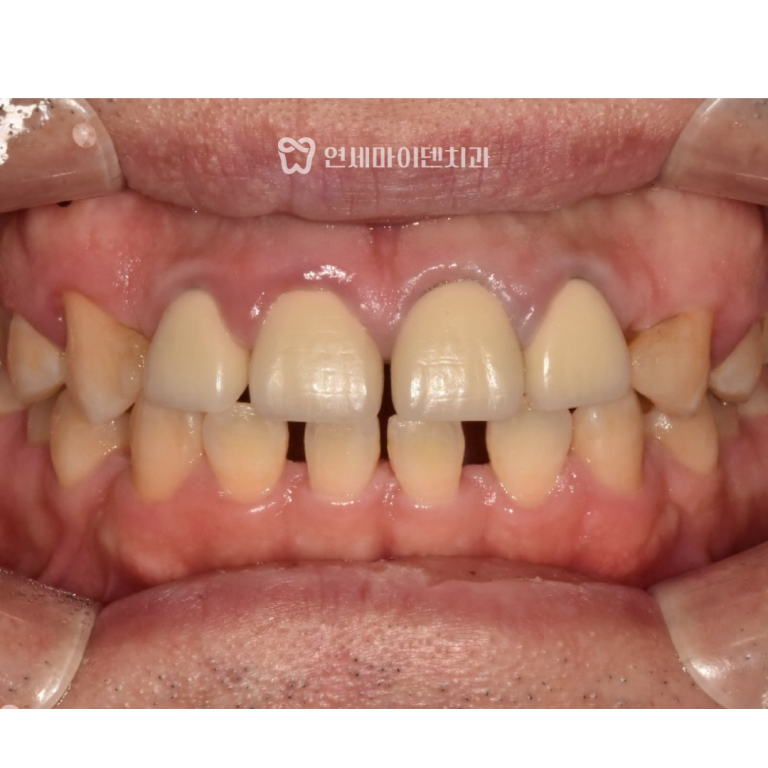

최종적으로는

- 임플란트 크라운이 완성되었고,

- 교합과 주변 치아의 움직임 없이 안정적인 결과를 얻을 수 있었습니다.